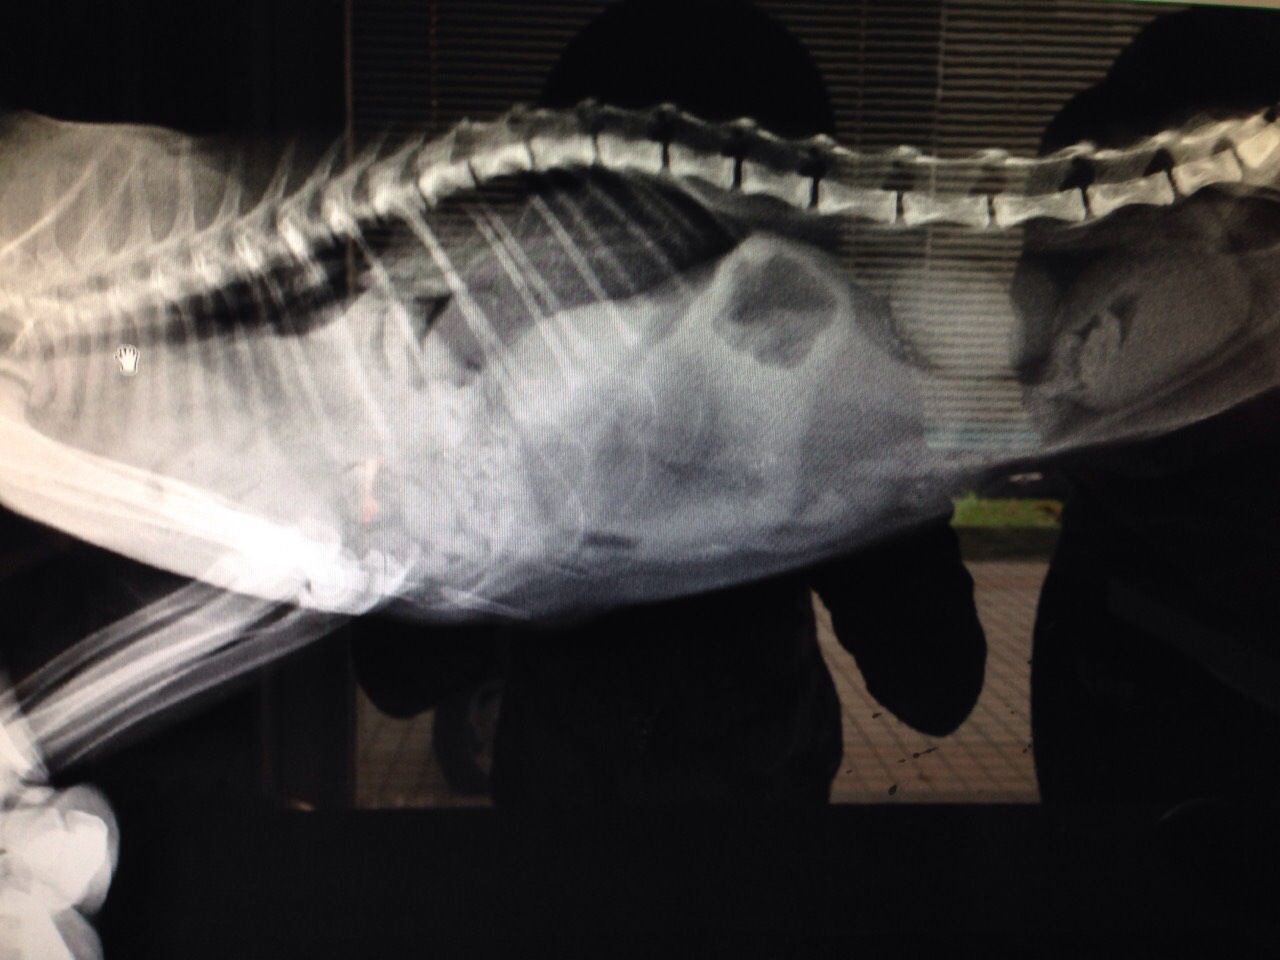

這次回去他狀況很差,肚子凹陷,食慾不佳,呼吸大又急促,想說檢查一下好送養,以為他只是營養不良,結果是胸腔赫尼亞,腸子佔胸腔1/2,呼吸窘迫,精神食慾不佳,貧血很嚴重,動手術才有存活機會。

12/16 醫生判定急需手術,開刀後發現除了腸子,整個肝臟都掉進胸腔,腸子有些發炎。